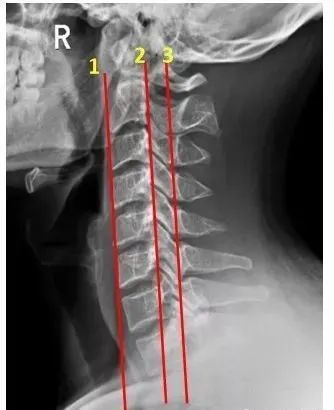

这是一个正常,中立位的颅骨和颈椎

颈椎病 x 线诊断